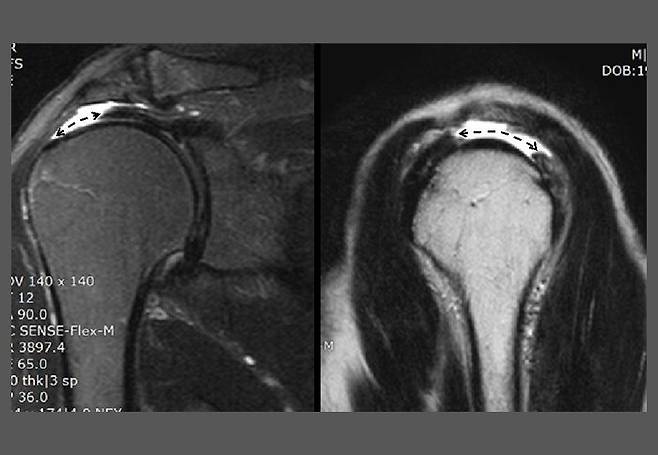

골프를 엄청 즐기는 72세 남성이 심한 오른쪽 어깨 통증으로 진료실을 찾는다. MRI를 확인하니 회전근개 힘줄 중 가장 잘 끊어지는 극상근 힘줄이 전층(全層)으로 파열되어 있었다(그림 1). 보통, 극상근 힘줄 전층 파열은 양말에 구멍이 나듯이 일부 부위에만 전층 결손이 생기는데 이분은 상당히 광범위한 전층 결손으로 완전 파열에 가까웠다. 극상근 근육 자체의 위축이 심한 것으로 봐서 파열이 오래전부터 있었던 것으로 추정된다.

병력을 확인해보니 지난 몇 년 동안 가끔 어깨가 아팠고 작년에 심하게 아파서 어깨에 주사를 맞고 회전근개 근력 강화 운동을 하였다고 한다. 아마도 수년 전부터 파열이 시작되었던 것으로 생각된다. 그런데 힘줄이 찢어지고 있는 근육에 강화 운동을 한 것은 성급했던 것으로 보인다.

최근 한 달 전부터 통증이 심해졌고 이후 4일 연속 골프를 친 후 더 악화하였다고 한다. 파열이 된 지 오랜 시간이 지났고 그동안 잘 적응하고 있었으므로 수술적 치료보다는 주사로 통증을 호전시킨 다음 회전근개 힘줄에 좋은 운동을 충실히 하는 방향으로 치료 방침을 정하였다.